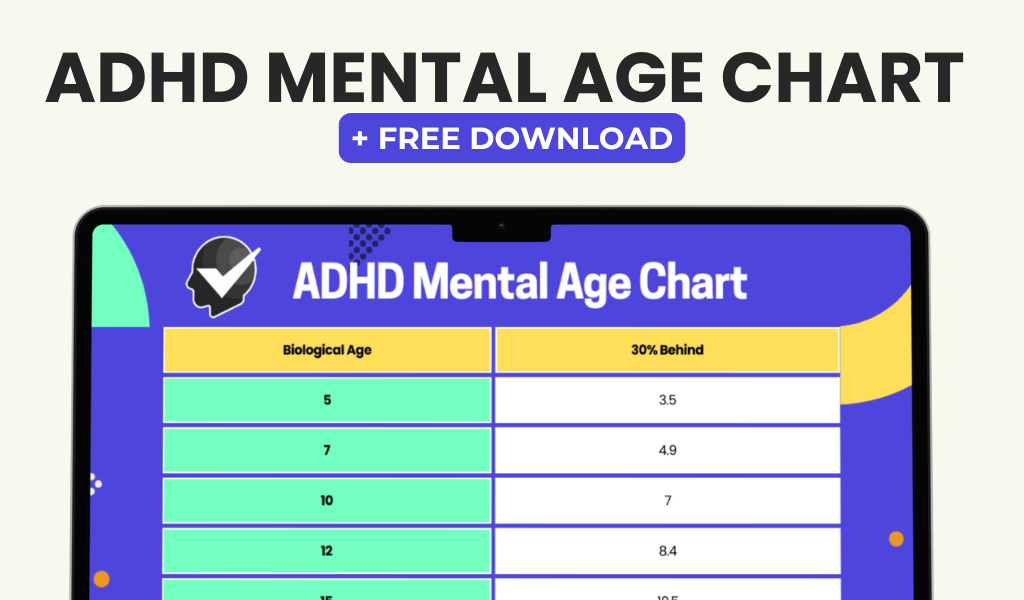

ADHD, or Attention Deficit Hyperactivity Disorder, is a neurodevelopmental condition affecting both children and adults. Its primary symptoms include inattention, hyperactivity, and impulsivity. Children with ADHD may exhibit difficulties in